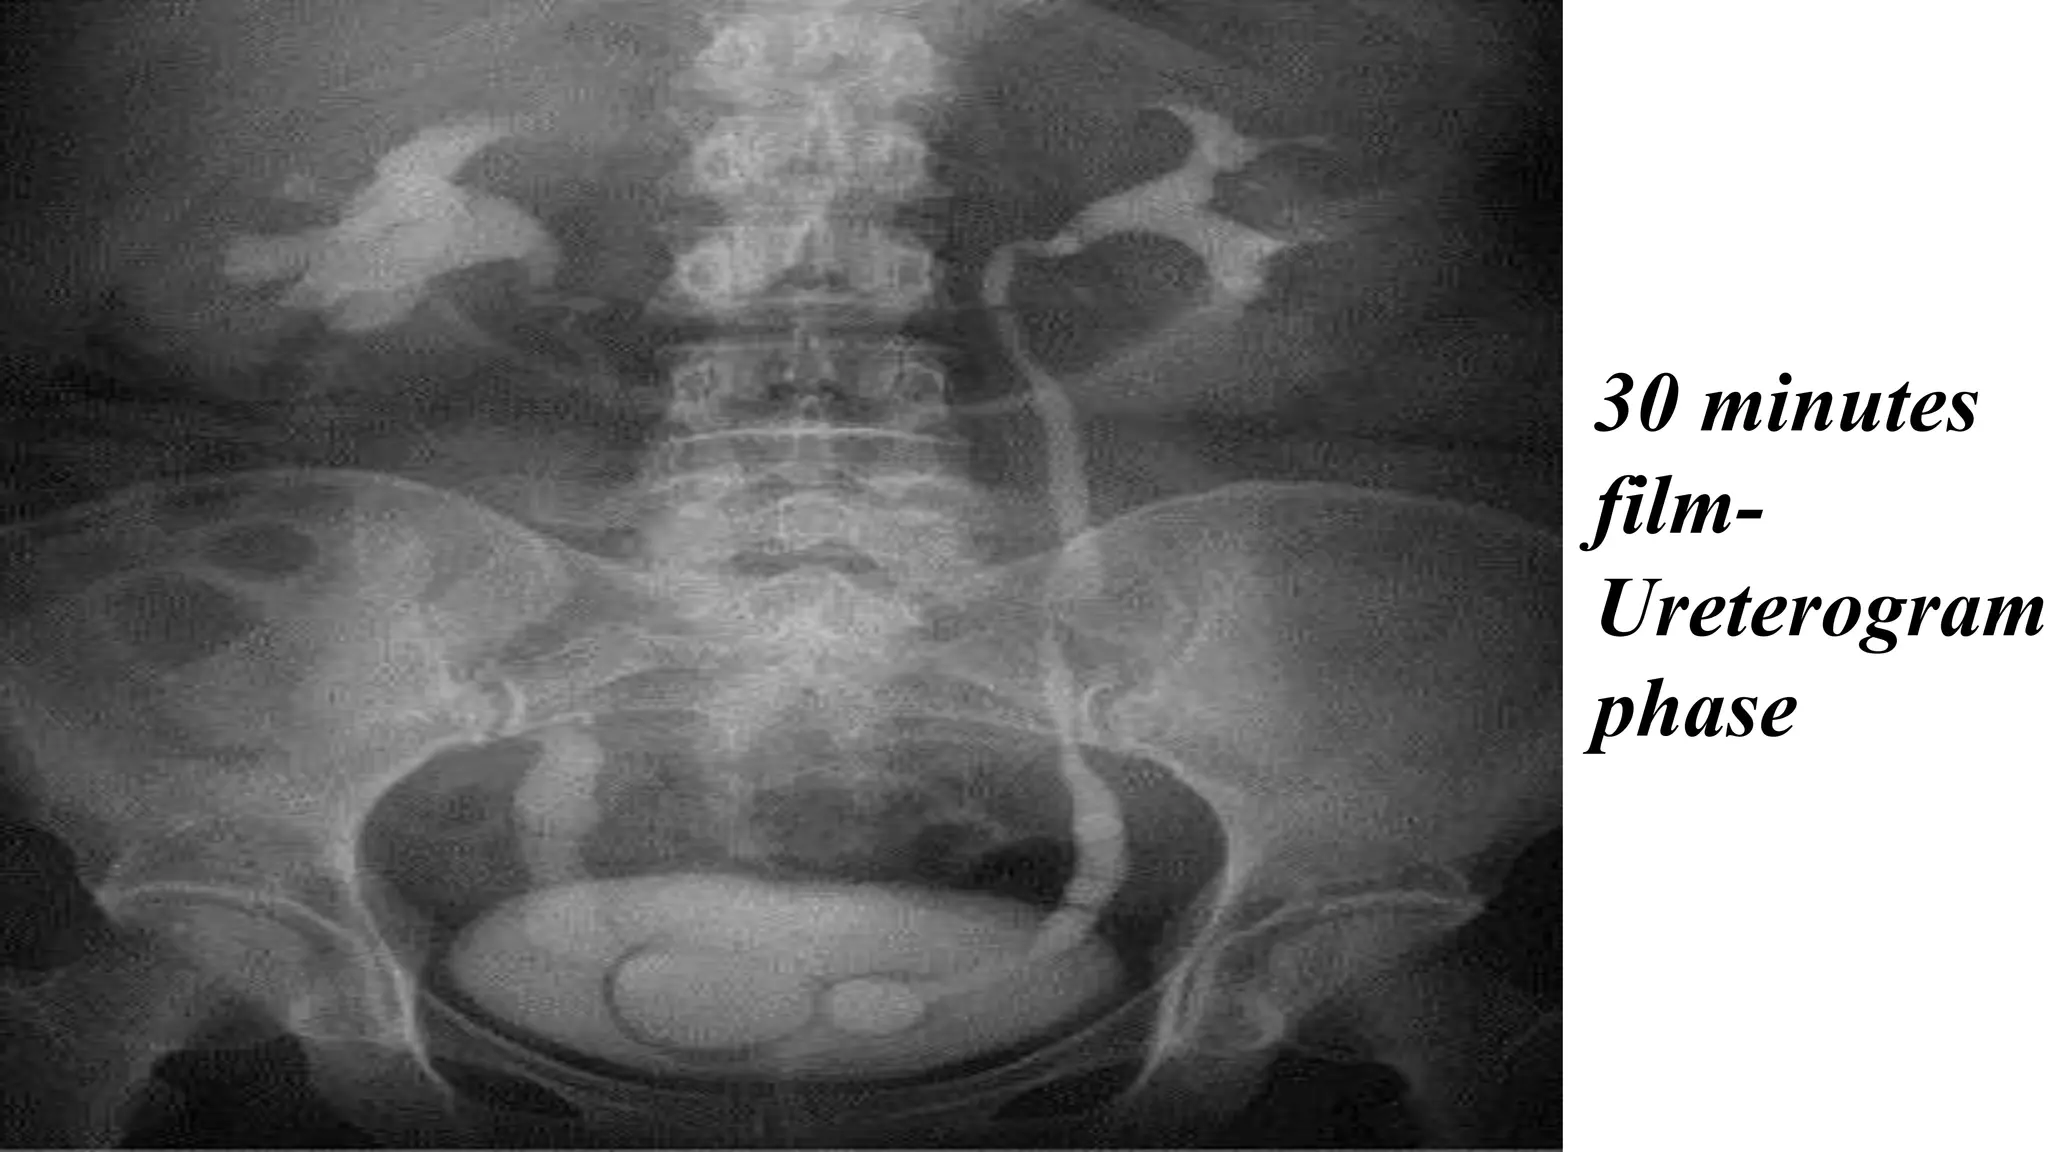

30 minutes film (Ureterogram

phase) :

Is there any collecting systems and ureters dilatation or

filling defect? (normal ureter filling is rarely demonstrate

the whole ureter from proximal to distal as there is a

peristaltic wave )

30 minutes

film-

Ureterogram

phase

30 minutes film(Ureterogram phase) : Is there any collecting systems and ureters dilatation or filling defect? (normal ureter filling is rarely demonstrate the whole ureter from proximal to distal as there is a peristaltic wave )